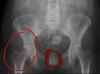

Это тазобедренный сустав

От нагрузки он может болеть